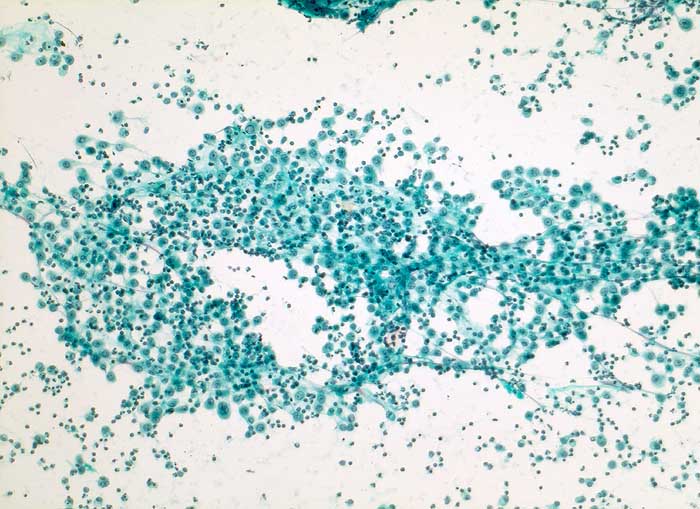

reaktiv veränderte Mesothelien

Aszites

Aszites: Flächenhafte lockere Verbände grossleibiger aktivierter Mesothelzellen und zahlreiche Entzündungszellen.

Dieses immunhistochemische Markerprofil, insbesondere die deutliche Positivität für den Mesothel-Marker Calretinin und fehlende Expression des Epithelmarkers Ber-EP4, passen am ehesten zu Zellen mesothelialen Ursprungs. Auch Zytokeratin 7 wird in normalen Mesothelien typischerweise exprimiert. Insgesamt sprechen die Befunde für ausgeprägte reaktive Veränderungen und gegen ein Karzinom. Insbesondere bei Leberzirrhose werden gelegentlich schwere reaktive Mesothelveränderungen im Aszites beobachtet, die zytologisch ein Karzinom vortäuschen können.

Zytologie

100